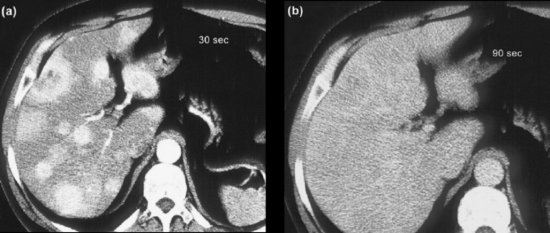

Exames de imagem são fundamentais para localizar o tumor primário, identificar sítios de doença metastática e avaliar a resposta ao tratamento, além de investigar a expressão de receptores de somatostatina. Tomografias (TC) e ressonâncias (RNM) são os métodos anatômicos mais empregados, mas cuidados técnicos são essenciais para otimizar a sensibilidade dos exames. A RNM é ligeiramente superior à TC, principalmente na avaliação do fígado e do pâncreas. Metástases hepáticas de TNE podem ser de difícil identificação à TC, uma vez que são comumente isodensas em relação ao fígado nas imagens de fase venosa portal (figura 1). Por esse motivo, a realização de exame trifásico é recomendada (VAN ESSEN, 2014). A avaliação de resposta por RECISTtem limitações em TNE, assim como em outras neoplasias em que agentes biológicos citostáticos são parte importante do tratamento. Apesar disso, os critérios RECIST seguem sendo utilizados nos maiores estudos clínicos de TNE.

Figura 1. TC de abdome em paciente com tumor neuroendócrino com metástases hepáticas após 30 segundos (a) e 90 segundos (b) da injeção do meio de contraste. O realce das lesões desaparece na fase venosa. Adaptado de Rockall e Reznek, 2007.